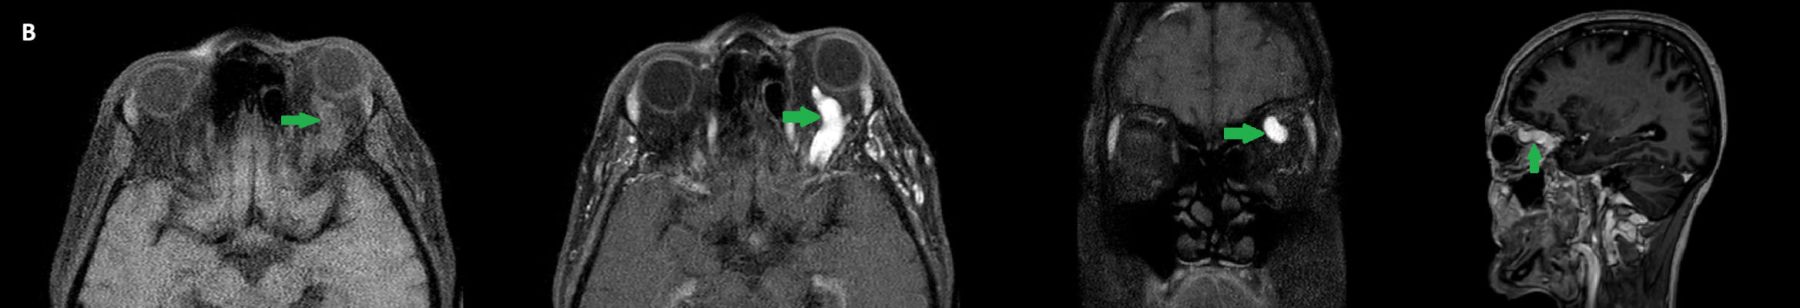

- B) Pre ve post-kontrast yağ basklılı T1A görüntüler incelendiğinde superior oftalmik venin (oklar) kontrast madde verildikten sonra homojen dolum gösterdiği, dilate ve tortiyoze görünümde olduğu izleniyor.

- BT ve MRG: Propitozis, ekstraokuler kaslarda genişleme, superior oftalmik vende genişleme ve tortiyozite, ipsilateral kavernöz sinüste genişleme gösterilebilir. Serebral venöz konjesyonu olan ve intrakraniyal basınçları yükselen hastalarda serebral ödem, hemoraji, leptomeningeal ve kortikal venlerin dilastasyonunu görülebilir. Bunlara ek olarak travmaya sekonder olgularda BT ile eşlik eden fraktürler gösterilebilir.